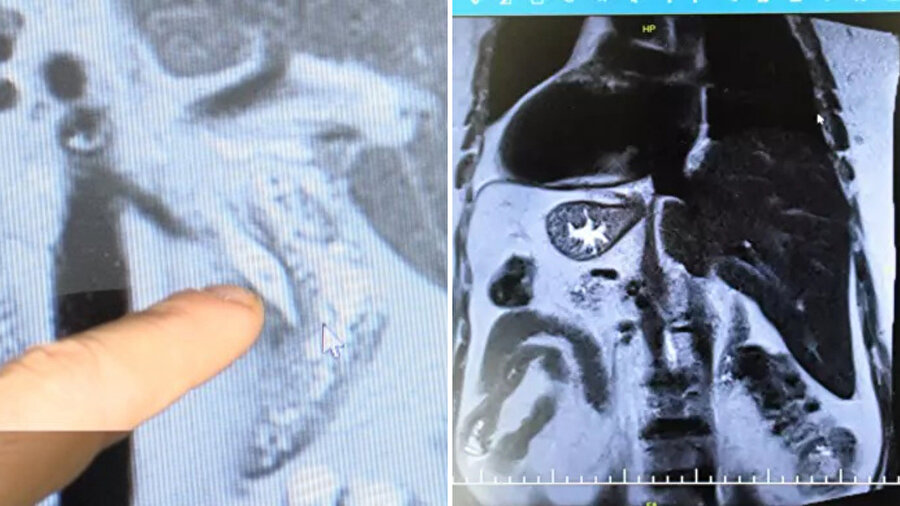

Uzun süredir mide ağrıları yaşayan ve ardı ardına hastanelere gitmesine rağmen net bir tanı konamayan Aslan, son olarak Gaziantep Şehir Hastanesi’ne başvurdu. Burada yapılan detaylı incelemelerde Aslan’ın kalbinin sağda, midesinin ve dalağının yine sağ tarafta; karaciğer ve safra kesesinin ise solda olduğu tespit edildi.

“Tüm organların ters yerleştiğini MR’da gördük”

“Hasta karın ağrısı şikâyetiyle geldi. MR görüntülemede tüm organların tam tersi şekilde yerleştiğini gördük. Aynı zamanda safra kanalında taş vardı ve tekrarlayan pankreatit atakları geçiriyordu. RCP işleminde hastayı ters pozisyonda almak zorunda kaldık. Oldukça zorlu bir işlem olmasına rağmen başarılı bir şekilde tamamladık” dedi.